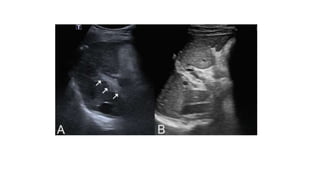

• Ultrasound and Doppler-

• Liver is either normal, enlarged, or small and shrunken.

• Unlike cirrhosis, the liver surface is smooth in patients with NCPF.

• Portal venous axis and intrahepatic portal tracts have echogenic wall

thickening often >3mm from periportal fibrosis .

• Periportal fibrosis can also have a layered appearance with alternative

echogenicity and hypoechogenicity .

• Massive splenomegaly and normal splenoportal axis are hallmarks of

NCPF.

• Doppler examination can reveal portal vein thrombosis, a known

complication of NCPF.